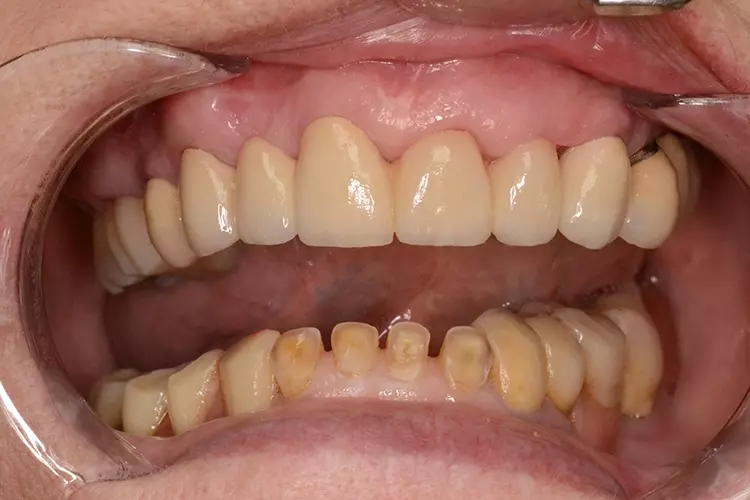

Neuversorgung Oberkieferfront auf Altimplantat 21

Die 49-jährige Patientin beklagte die ungleiche Höhe der Schneidekanten an den Kronen 11 und 21. In diesem Zusammenhang wurde das Gesamterscheinungsbild analysiert und entschieden, die Zähne 13-23 zu überkronen und dabei die Altkronen an 11 und an dem Implantat 21 zu erneuern. Die verschachtelt stehenden Zähne im Unterkiefer sollen im Nachgang per Aligner-Therapie ausgerichtet werden.

Dabei wurde die beabsichtigte Situation im Vorab per Wax-up simuliert. Beim Entfernen der Altkrone 21 wurde ersichtlich, dass ein Titanabutment eingesetzt wurde, an dem sich Konkremente und Zementreste befanden, die zu einer marginalen Mukositis am Implantat führten.